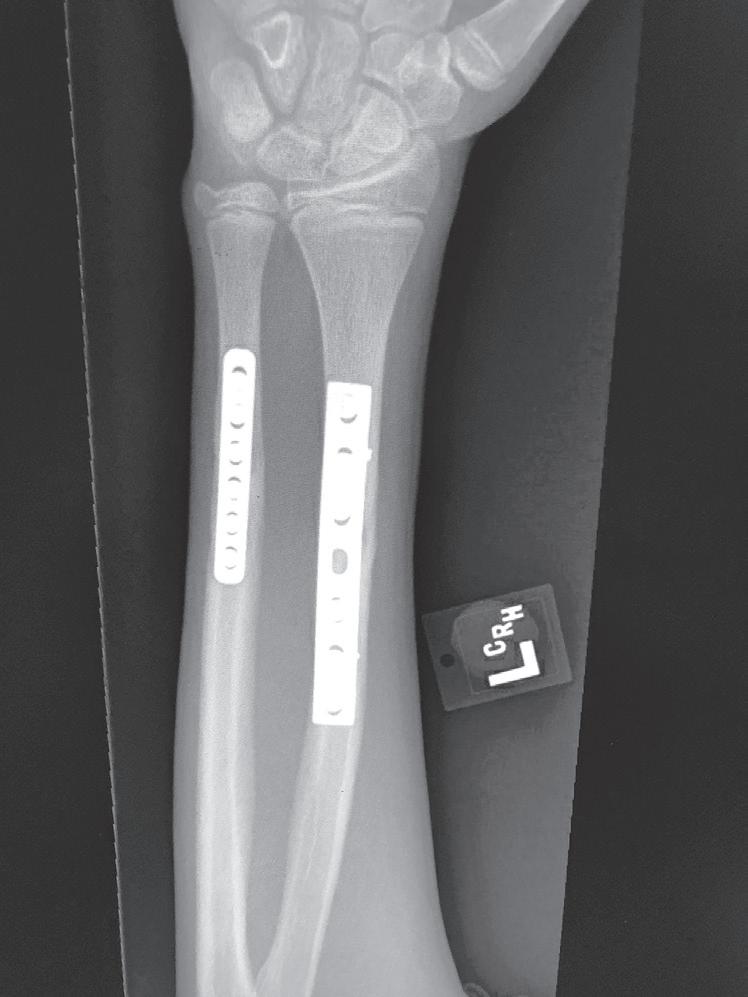

Tissue differentiation during the reparative phase is strongly influenced by local mechanical factors. Fracture stability has a critical effect on bone healing. Fracture healing is classically divided into primary and secondary healing. Primary healing results from rigid stabilization (i.e., plate immobilization) and involves a direct attempt by the cortex to bridge the fracture gap. Bridging occurs through direct haversian remodeling by intramembranous bone formation (Fig. 1.2A, B).

Secondary healing results from treatment of fractures with less rigid methods (i.e., fracture bracing, casts). In secondary healing, more motion at the fracture site leads to lower

Fig. 1.2 Anteroposterior (A) and lateral (B) radiographs of a forearm in a 15-year-old male who underwent open reduction and internal fixation with plates/screws. The fracture healing demonstrates primary bone healing with rigid fixation. An anteroposterior radiograph of a forearm in a 5-year-old at the time of original cast immobilization (C) and at 10 weeks (D) with complete fracture union demonstrates secondary bone healing. The motion that occurs with secondary bone healing results in abundant callus formation.

oxygen tension, and more cartilage is formed. Motion at the fracture site, the presence of a fracture gap, and an intact soft tissue envelope all encourage the formation of abundant callus (Fig. 1.2C, D). The increased diameter of the callus enhances biomechanical stability because the rigidity of the bone is proportional to its radius. The callus formed subsequently undergoes endochondral ossification. Ideal fracture treatment involves enough rigidity to ensure adequate vessel ingrowth, followed by progressive loading and motion to stimulate ample callus formation.36,40